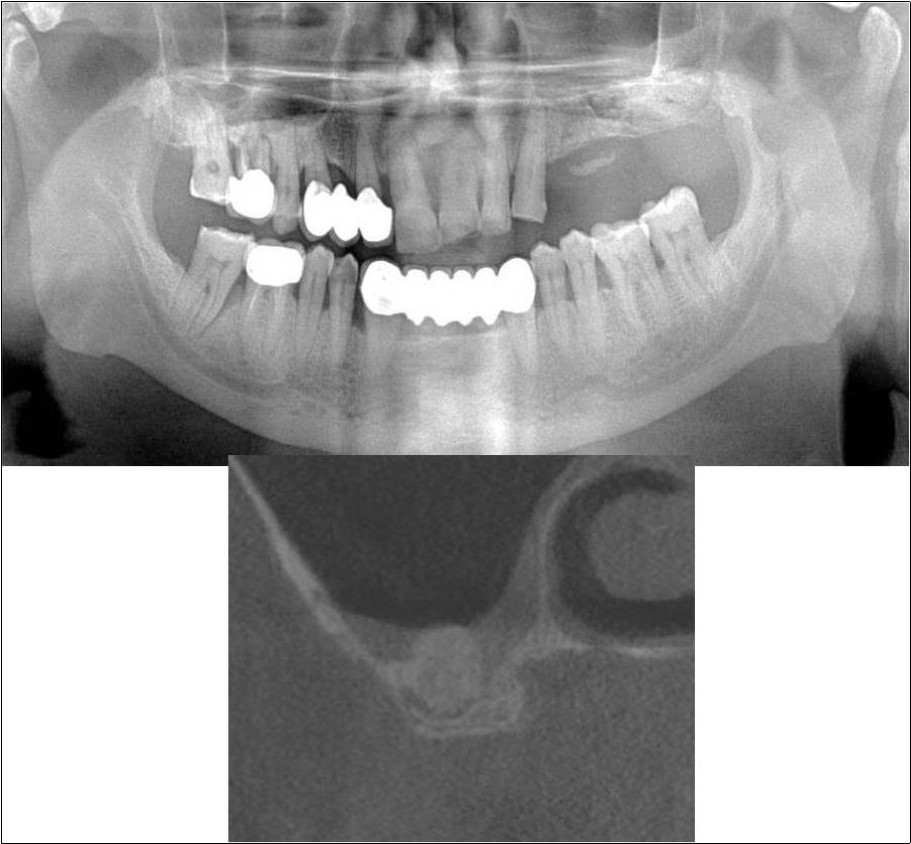

Figure 15.a,b. Pre-treatment OPG and cross section of CBCT showing residual alveolar bone height for Case No.5;

Figure 16.a,b. Post-treatment OPG and cross section of CBCT showing residual alveolar bone height for Case No.5;